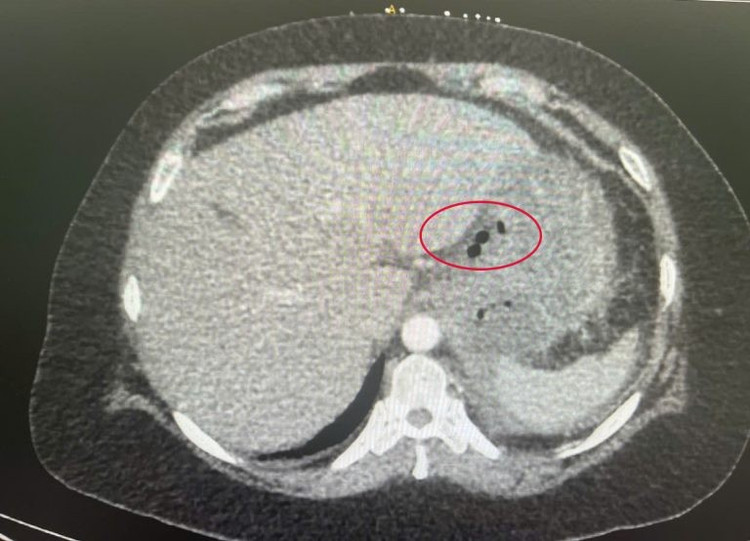

Hình ảnh cận lâm sàng cho thấy xương cá trong dạ dày - Ảnh BVCC

Ngay sau đó, ê-kíp phẫu thuật tiến hành lấy dị vật, làm sạch ổ áp xe, khâu lỗ thủng dạ dày bằng mũi chỉ chữ X, đặt dẫn lưu tại nhiều vị trí để đảm bảo dịch thoát tốt, hạn chế nguy cơ nhiễm trùng sau mổ.